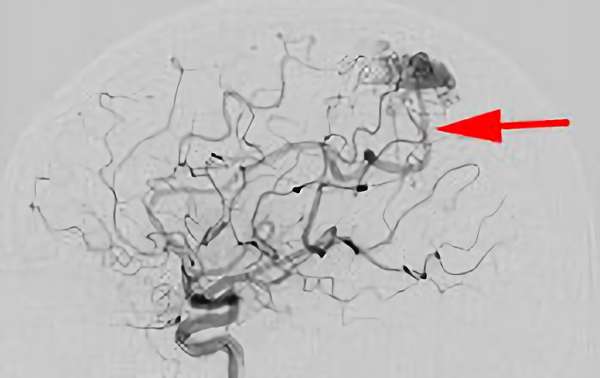

No.1583 手術前

No.1583 手術中

No.1583 手術後